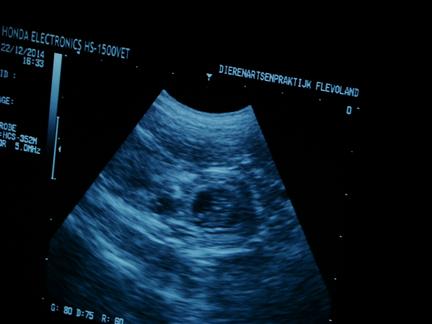

| maar in de donkere ronde vlekken |

zie je witte lijntjes |

| en dat zijn .......... de puppies :-) |

ook zijn de hartjes al aan het kloppen, allemaal prachtig om te zien |